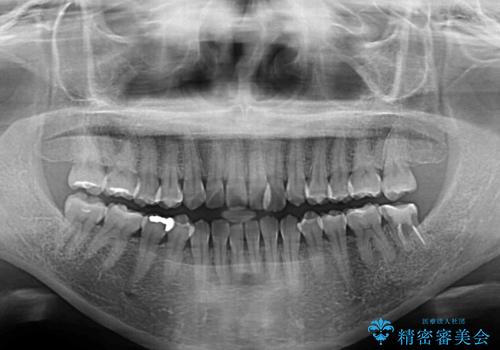

舌の突出癖が認められたため、デコボコ改善に伴い前歯が前突する可能性があったため、舌のトレーニングをしっかりと行うよう指導しながら治療を進めることとしました。

左下の奥歯は根管治療後に放置されていたため、咬み合わせを調整しながら矯正治療を行い、最後にオールセラミッククラウンにて補綴治療を行うこととしました。